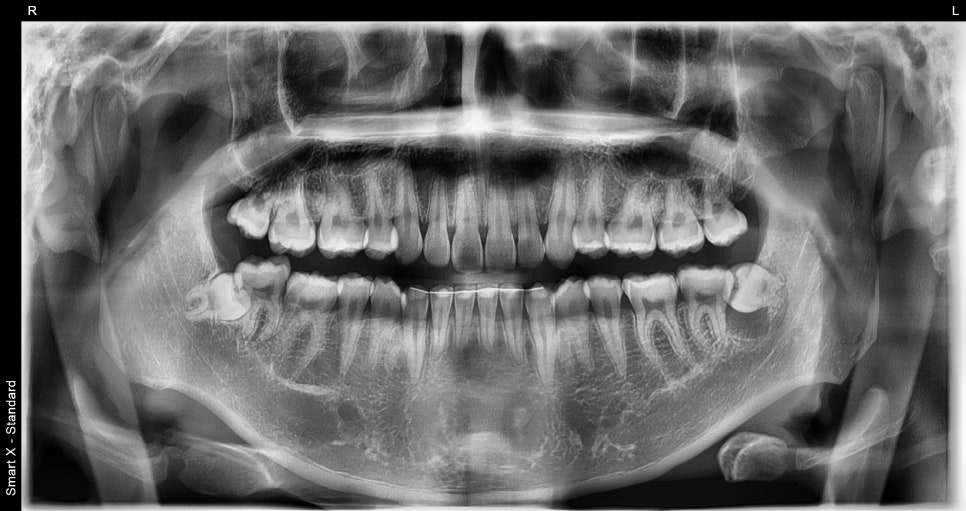

내원당시 초진 엑스레이 사진

파노라마 및 소형 엑스레이 촬영 결과,

하악 좌측 제3대구치 아래 6mm 이상의

방사선 투과성 병소(검게 보이는 낭종 조직)가 확인되었고,

치아 낭종으로 의심되었습니다.